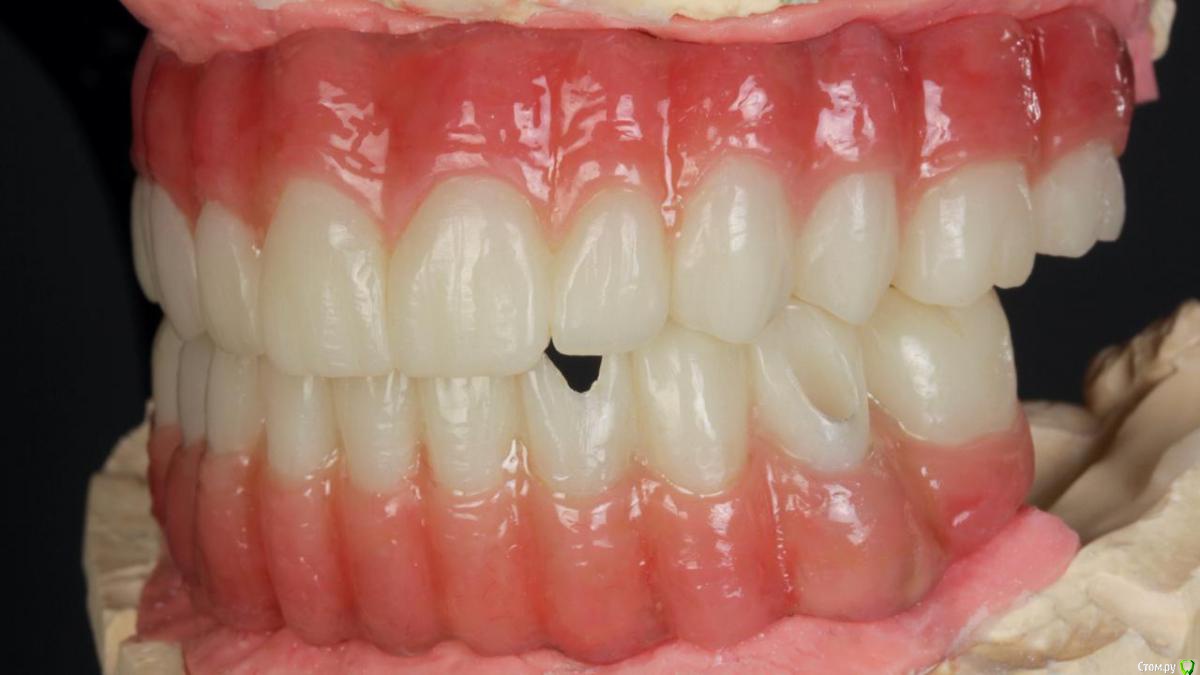

Bier Опубликовано 10 февраля, 2020 Поделиться Опубликовано 10 февраля, 2020 Хирургия в седации 3,5 часа + редукция гребня. По шаблону под пилот. Все мультиюниты были заранее выбраны техником и четко сели.Временные армированные протезы (лазерное спекание) 8 Ссылка на комментарий

Bier Опубликовано 11 февраля, 2020 Автор Поделиться Опубликовано 11 февраля, 2020 А какую финальную конструкцию планируете?Металло композит или металлический каркас с индивидуальными коронками из керамики. Скорее всего на одну челюсть так, другую так. Ссылка на комментарий